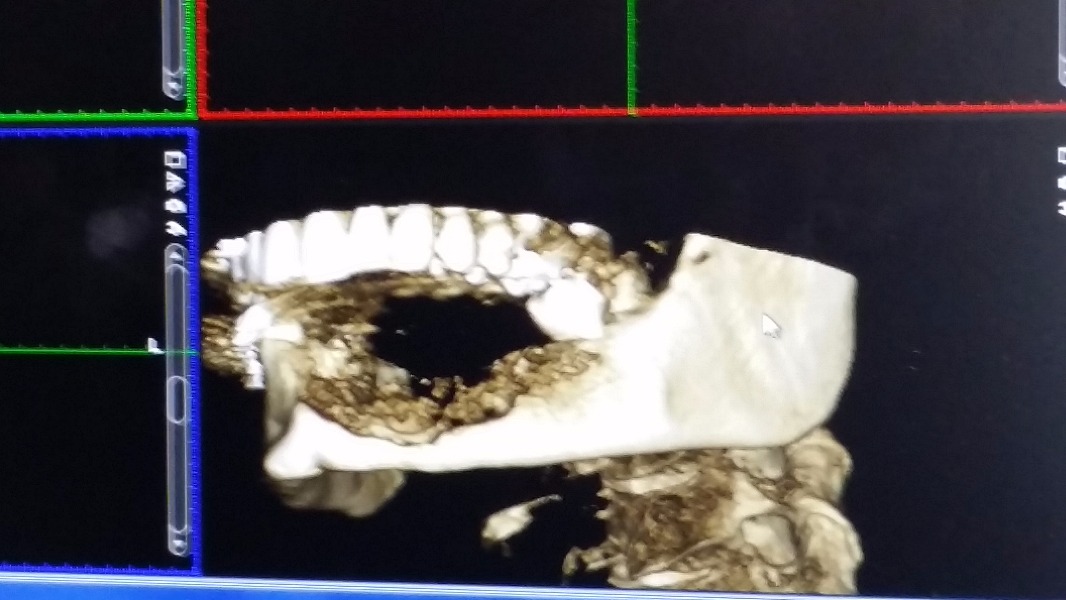

As most of you know, over the last year or so Kim has been battling medical issues after finding a Giant Cell Granuloma tumor in her bottom left jaw. Giant Cell Granuloma tumors are bone eating and although the original tumor was benign, the only way to ensure that it would stop growing or continuing to eat the bones in her jaw was to remove it. Of course, with tumor removal in the jaw came the loss of teeth and bones. After the first surgery in December of 2014, Kim faced the challenges of recovery plus an additional bone graph surgery in July of 2015 where part of her hip bone was surgically removed and placed in her jaw. After facing yet another round of recovery, this time in both her hip and her jaw, in December of 2015 the doctor's found a new tumor on the right side of her jaw that seems to be of the same type as the previous.

Following the biopsy, and if the doctor's anticipations of it being a second Giant Cell Granuloma tumor are true, that tumor, along with the teeth and part of the jaw it effects will need to be removed. At that point, Kim will have (hopefully) two remaining teeth in her bottom jaw.

In anticipation of the second tumor, Kim is still needing to address the reconstruction of the removal of the original tumor. At this stage, one-year post surgery, the plan is to begin the preparation for porcelain implants, or a new set of teeth. In order to do this, Kim will face a third surgery in which five metal posts will be implanted into the graphed bone in her jaw. This surgery cost is roughly $9,795. However, the quote only includes 30 minutes of general anesthesia, and the doctors anticipate surgery could take up to an hour and a half.

Following the third surgery, if all goes as planned, it should take about 4-6 months of tissue recovery before Kim faces another surgery in which the surgeon will re-expose the five metal posts and cap them in order to prevent further tissue growth. Once the posts are capped, Kim will face another 4-6 months of healing. This fourth surgery has yet to be quoted, but given previous experiences it is only fair to assume that it will be costly.

Once these two surgeries regarding the metal posts have occurred and recovery is successful, Kim will finally be given a new set of teeth on the left side. (Remember, this is without any knowledge of that second tumor of the right or the cost that will come with it). Although this seems far off in time at this point, the initial cost covers all surgeries and stages of the process regarding the porcelain implants. The current quote for the teeth and jaw replacement is $19,542.